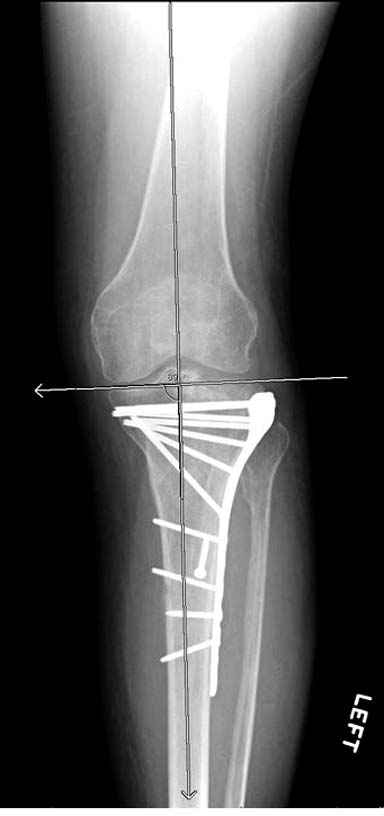

На вашем место я бы подождал с фиксацией до готовности кожных покровов, и за это время можно было подобрать соответствующий фиксатор, т.е более длинная пластина снаружи и медиальная пластина на апексе перелома как подпорка. Здесь приемлем как раз минимальный доступ.

Если там действительная импрессия, пустое место без структуральных заполнителей, кость или синтетические материалы, не восстановится, а образуется коллапс, и ось конечности поведет после нагрузки. Кроме того там возможно "болт стяжка"?, в медиальной стороне выступает за кортекс, можно было укоротить! Потом создается впечатление, что не соответствуют мыщелки большеберцовой и бедренной костей? Покажите снимок.

Здесь пару случаев для сравнения,...в первых 1-4 слайдах метод фиксации одним фиксатором, как видно после 8 месяцев сохранилась ось. С 5 по 9 вариант двумя пластинами...